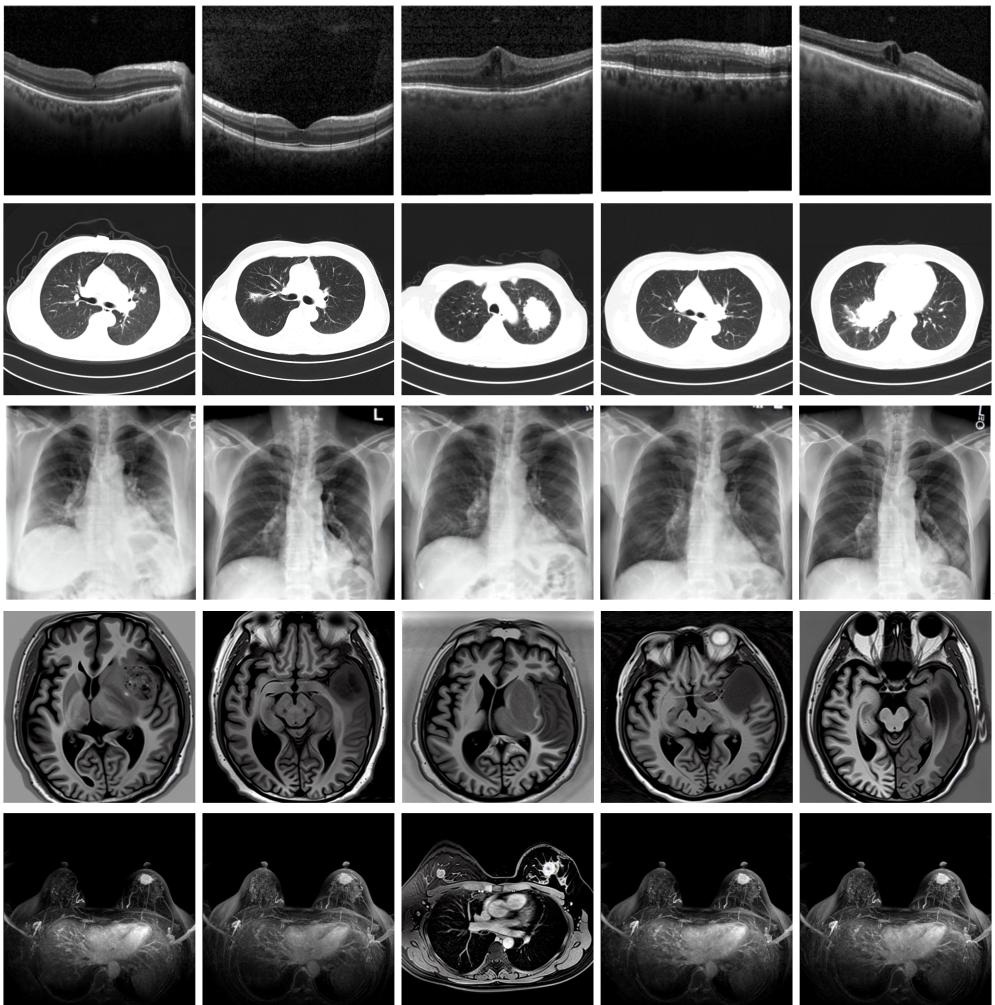

圖為由MINIM生成的高質(zhì)量醫(yī)學(xué)合成圖像(受訪者供圖)

“目前公開的醫(yī)學(xué)影像數(shù)據(jù)非常有限,我們建立的生成式模型有望解決訓(xùn)練數(shù)據(jù)不夠的問題。”北京大學(xué)未來技術(shù)學(xué)院助理研究員王勁卓說,研究團隊利用多種器官在CT、X光、磁共振等不同成像方式下的高質(zhì)量影像文本配對數(shù)據(jù)進行訓(xùn)練,最終生成海量的醫(yī)學(xué)合成影像,其在圖像特征、細節(jié)呈現(xiàn)等多方面都與真實醫(yī)學(xué)圖像高度一致。

實驗結(jié)果顯示,MINIM生成的合成數(shù)據(jù)在醫(yī)生主觀評測指標(biāo)和多項客觀檢驗標(biāo)準(zhǔn)方面達國際領(lǐng)先水平,在臨床應(yīng)用中具有重要參考價值。在真實數(shù)據(jù)基礎(chǔ)上,使用20倍合成數(shù)據(jù)在眼科、胸科、腦科和乳腺科的多個醫(yī)學(xué)任務(wù)準(zhǔn)確率平均可提升12%至17%。